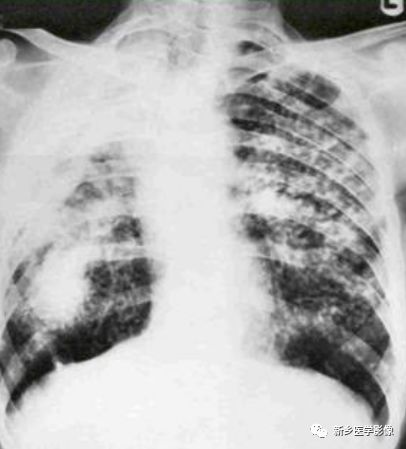

X线

单纯矽肺边缘清楚的小结节,直径常为2~5mm,但其范围常为1~10mm,主要累及上肺部和后肺。

复杂性矽肺可见大阴影,常发生在上肺部的中外带,并向肺门移动,在融合性肿块与胸膜间留下气肿的间隙。肿块可发生坏死形成空洞。

肺纹理改变:早期肺纹理增多、增粗,分支交叉,形成网状,晚期肺气肿加剧,肺纹理减少。

矽结节及其融合:矽结节表现为直径约3mm,边界清晰,致密孤立的结节,进展后融合成均匀致密团块,即大结节。常见于两肺上野外带。

肺门改变:肺门增大,密度增高。肺门淋巴结蛋壳样钙化。

肺气肿:弥漫性或局限性

胸膜改变:肋膈角变钝,胸膜增厚。

矽肺合并结核:肺尖或锁骨上下区